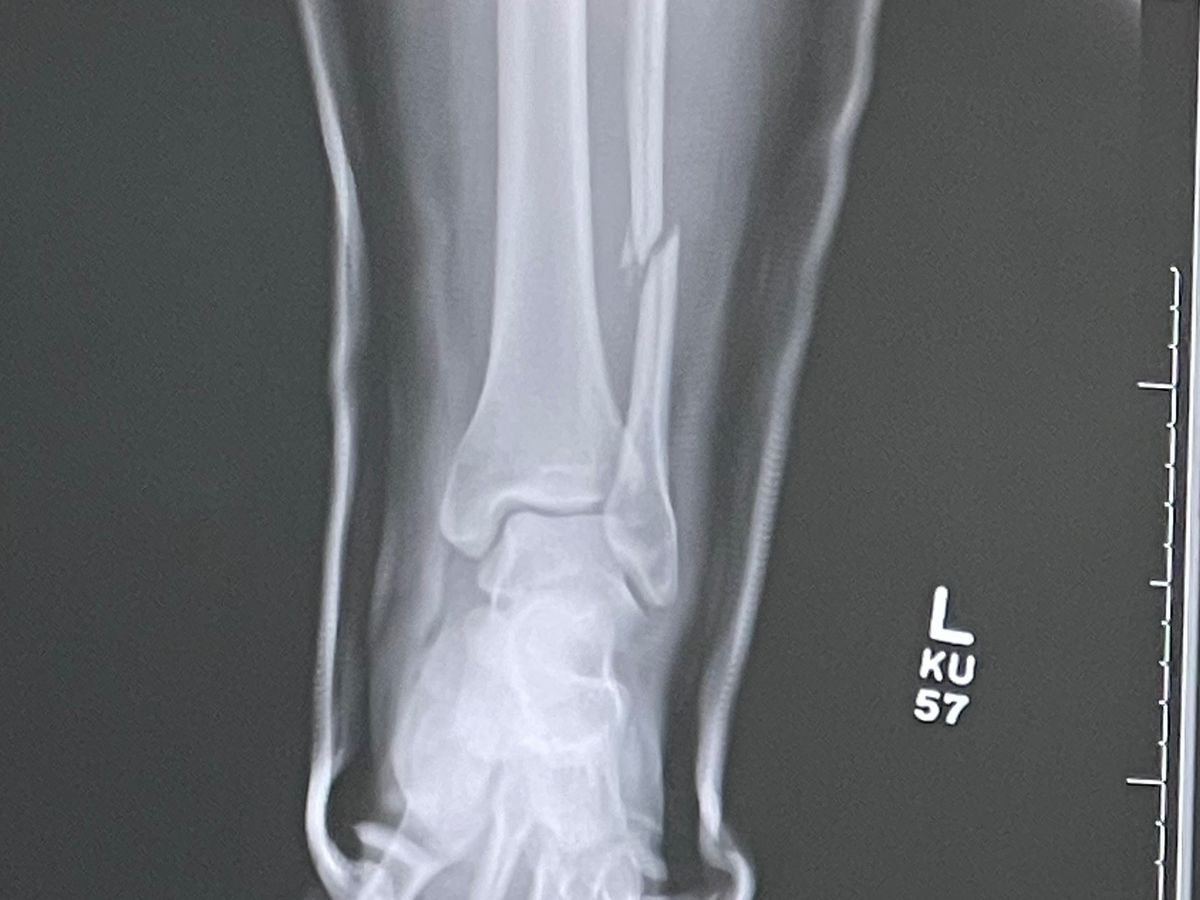

My name is Adriana. I had a terrible fall last Friday at CB Smith Park and ended up breaking my fibula and dislocating my tibia bone. At the ER, they were able to pop the tibia back into place, but I'm still left with my broken fibula. My United Health Group insurance from my job does not want to cover this surgery; they claim I have 0 surgical benefits. So, I'm left facing this huge bill for my surgery scheduled for Monday, Dec 9th. I know Christmas is around the corner, and this is my only Christmas wish. God bless you all, and thank you for reading this!